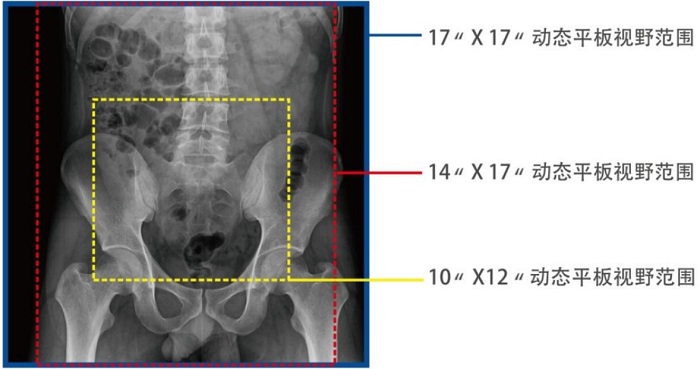

動態(tài)DRF在肛腸科檢查中優(yōu)勢明顯。首先,17×17英寸大幅面成像,對于食道、胃、腸、結(jié)腸等大范圍成像部位,可一次曝光完成,極大減少了患者的輻射劑量和檢查時間,且空間分辨率高,與傳統(tǒng)胃腸機(jī)相比,圖像質(zhì)量大幅提升。